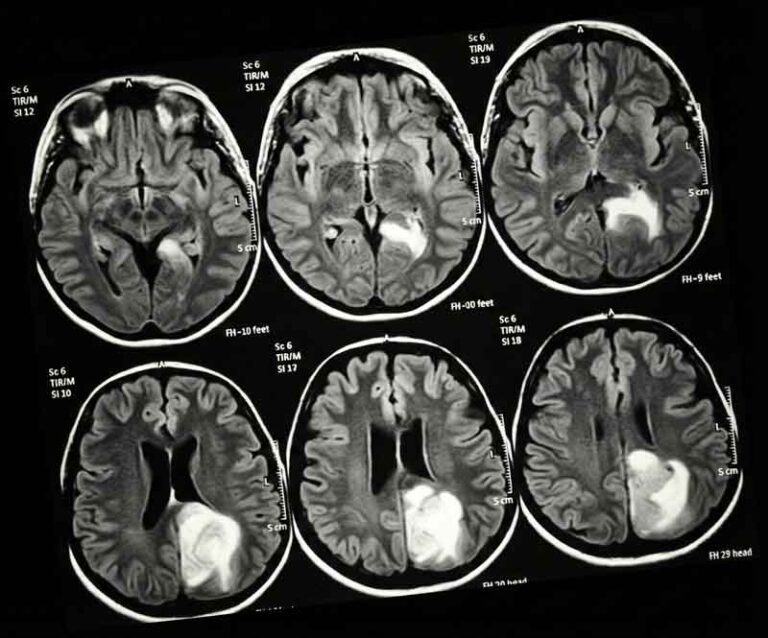

Malignant gliomas and Glioblastoma Multiforme (GBM) represent some of the most complex challenges in modern oncology. Fighting these aggressive tumors requires more than standard care; it demands a fusion of advanced microsurgical techniques and personalized immunotherapy.

Surgery is the first and most critical step in managing malignant astrocytoma and GBM. We utilize intraoperative neurophysiological monitoring and advanced microsurgical techniques to achieve maximal safe resection while preserving neurological function.